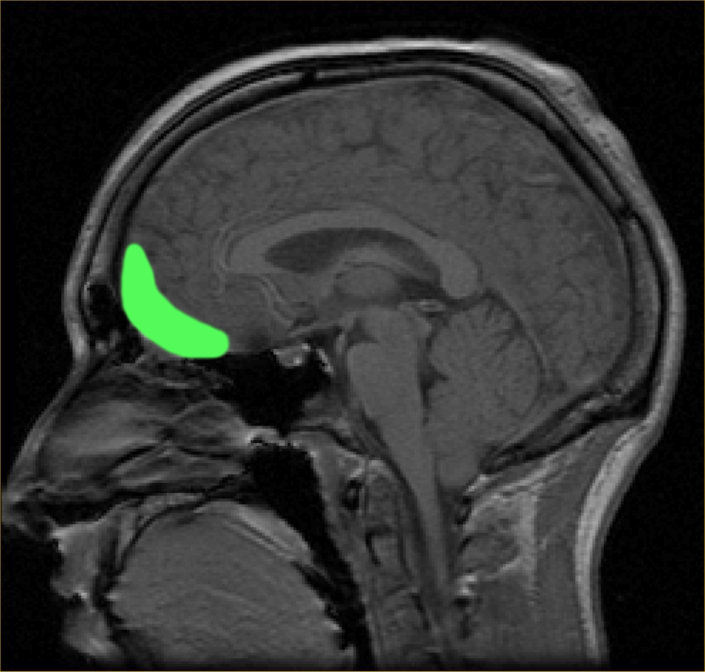

These days we know that the frontal lobe is tied to many, many functions, from decision-making and risk-assessment to short-term memory to social behaviour and empathy. The prefrontal area, namely the orbitofrontal cortex—the part of the brain that sits right behind your eye sockets—plays an important role in impulse control and planning. After his injury, Phineas Gage was famously “no longer Gage.” Some sources cite the extreme: that he was transformed overnight from a pleasant, hard-working young man into a drunken, aggressive, lazy, profane jerkface; others state that he’d lost ambition and any sort of money sense, that he was emotionally void.

Casey: Rachel Duncan experienced an injury similar—though less extreme—to Phineas Gage. The pencil shot through her eye (destroying the organ completely), and through into her brain, as Dr. Nealon said, leaving her with frontal lobe damage.

As Delphine interrogates her, we see that her memory appears to be intact. She answers Delphine’s questions to the best of her ability, seemingly on topic; she knows who she is, who Delphine is, and what Delphine wants. This is all consistent with frontal lobe damage, as this is a center for language motor functions, not memory or intelligence.

The pencil most likely did not hit far enough back to injure Broca’s area, because Rachel exhibits the signs of apraxia of speech, but not of Broca’s aphasia. Broca’s aphasia includes a similar inability to verbalize and incapacitated language motor skills, but it is also combined with an inability to sequence verbal thoughts. If Rachel had been experiencing Broca’s aphasia, she would not have been able to answer Delphine’s questions, and would most likely have just responded with muddled speech with no coherent meaning.